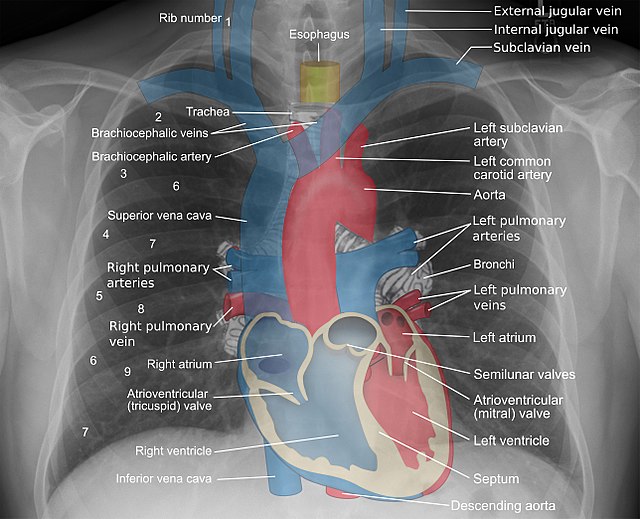

How To Diagnose Heart failure And When To Request For Echocardiogram.

Despite its name, CHF does not mean the heart has completely failed. However, CHF can be life threatening if left untreated. In general, more than half of all people with CHF survive for 5 years after diagnosis, according to a 2019 systematic review and meta‐analysis . About 35% survive for 10 years.